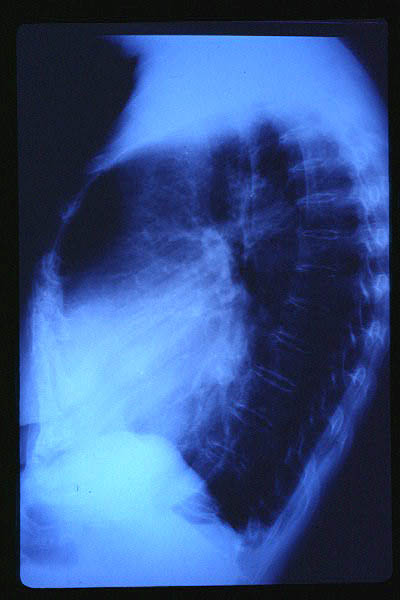

Tumoración mediastínica